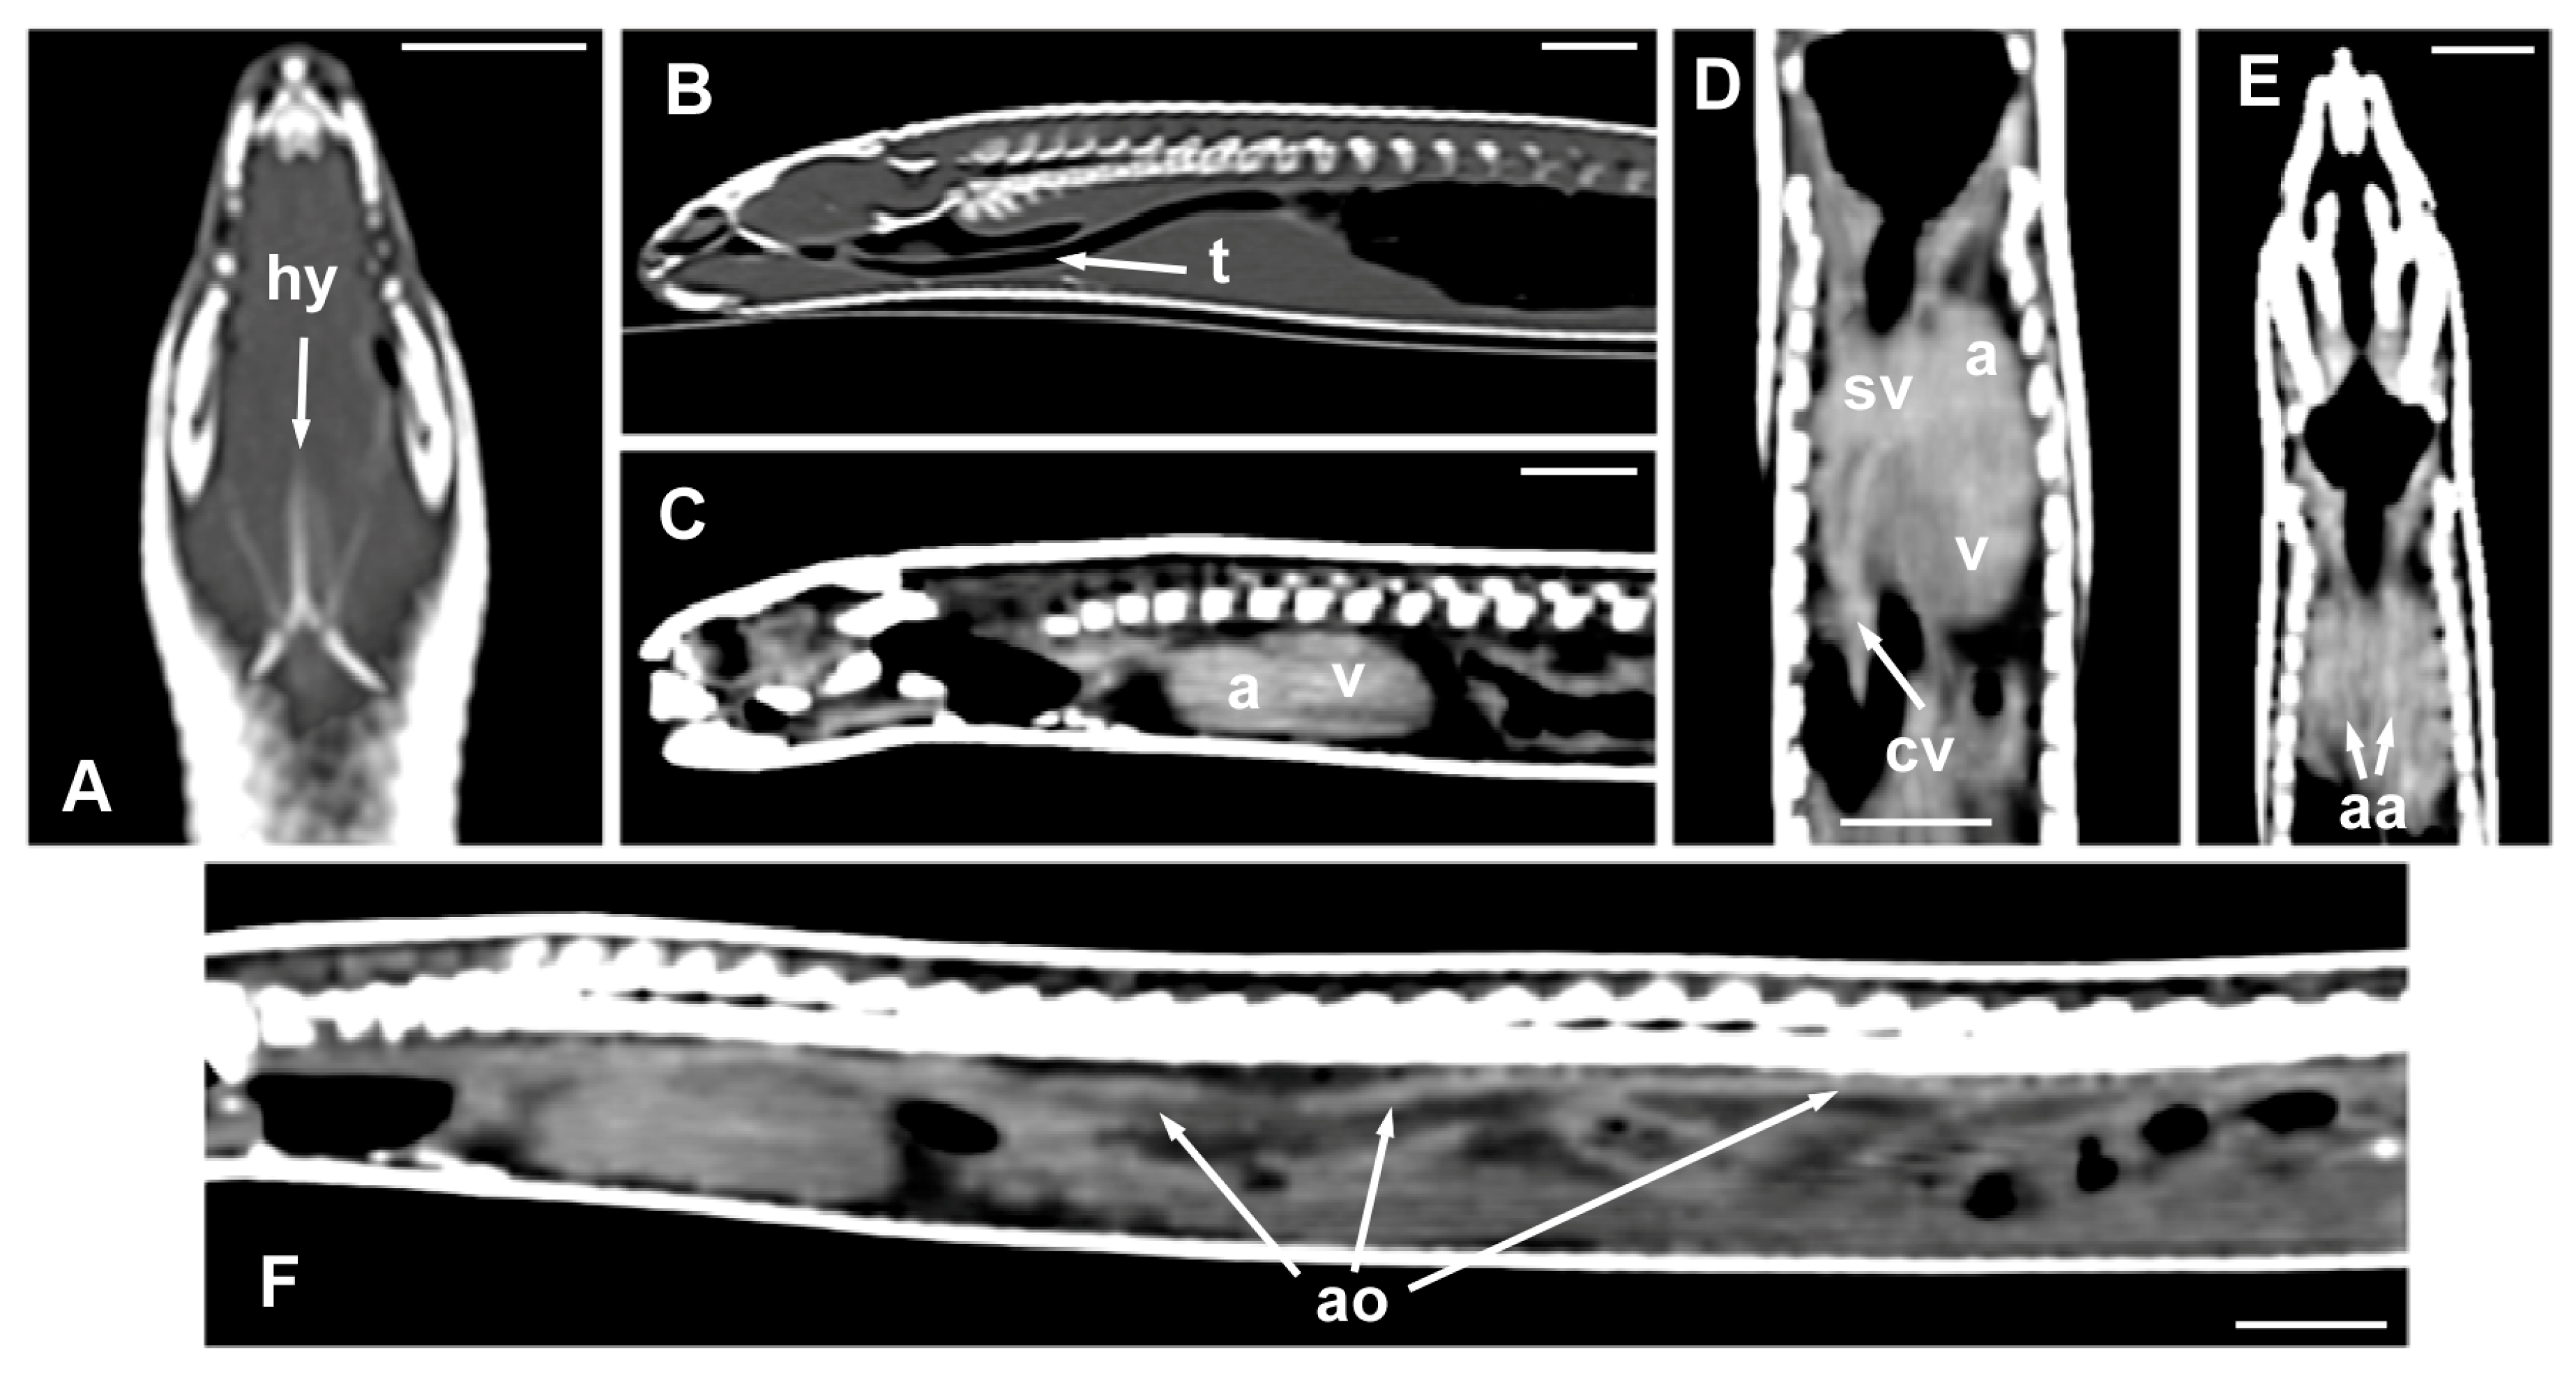

In general terms, the internal organs in many serpentiform species are elongated, arranged sequentially, or even compressed laterally. This is also true in the case of the Pseudopus apodus. Once the animal is opened, along the ventral midline, the presence of two powerful masticatory muscles (pterygoideus muscles) (Figure 5A,B), together with the hyoid bone that provides support to the tongue (Figure 5A), is notable. Only a portion of the hyoid bone can be seen in a dissection, compared to the full shape of the in situ bone with CT imaging (see below). The trachea is a membranous and cartilaginous flexible duct that extends from the larynx to the entry of the thoracic cavity (Figure 5A–D). As in other lizards, the tracheal rings are incomplete. Parallel to this, it is possible to identify the presence of two cranial cava veins. The heart is elongated and conically shaped, with two atria and a single ventricle (Figure 5B). There are two aortic arches (left and right), emerging from the heart, and a pulmonary trunk, which is subsequently divided into two pulmonary arteries (right and left). The aortic arches join to form the dorsal aorta, which runs through the entire coelomic cavity (Figure 5B,C). Immediately above the heart, it is possible to see the thyroid gland, which is small and rounded (Figure 5D).

Figure 5.

The images of the dissection of Pseudopus apodus in the ventral plane showing the hyoid bone (A), the trachea (A–D), the cranial cava vein, and aortic arches (B), the atria and ventricle (A,B), and the thyroid gland (D). See the list for abbreviations. Bar = 10 mm.

The morphology of the hyoid bone was most clearly observed in the dorsal plane, in the CT images obtained from the MPR reconstruction (Figure 6A). The trachea was clearly distinguished as a tubular structure containing gas in the lumen, extending from the glottis to the main bronchial bifurcation; the sagittal plane allowed the visualization of its entire length (Figure 6B). The heart and some great vessels were best identified in postcontrast images (Figure 6C–F). The dorsal and sagittal planes were the most suitable for observing the slight distinction between the atria and the ventricle of the heart (Figure 6C,D). On the contrary, the sinus venosus, the two cranial cava veins, and the aortic arches were most clearly observed in the dorsal plane (Figure 6D,E). The aorta was identified along the midline, just ventral to the spine, and was best observed in the sagittal plane (Figure 6F). The pulmonary trunk, divided into the left and the right pulmonary arteries, and the thyroid gland, were not identified in the CT images.

Figure 6.

The CT images of Pseudopus apodus in the dorsal (A,D,E) and sagittal (B,C,F) planes showing the hyoid bone (A), the trachea (B), the atria and ventricle (C,D), the sinus venosus and the two cranial cava veins (D), the aortic arches (E), and the dorsal aorta. The images (C–F) were obtained after contrast media administration. See the list for abbreviations. Bar = 10 mm.